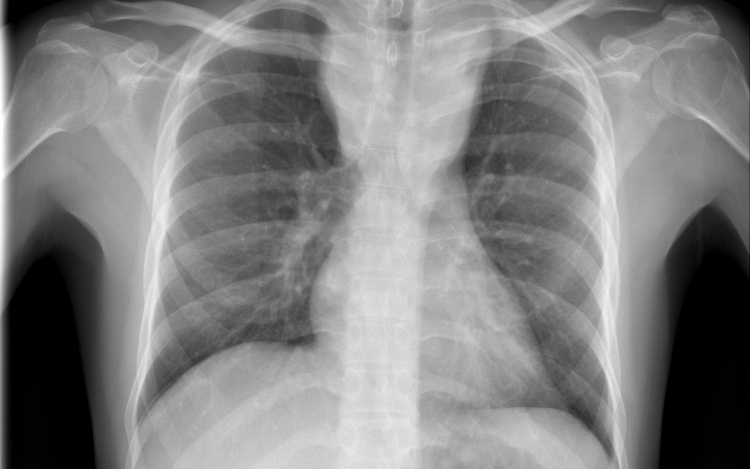

Magyarországon halnak meg a legtöbben tüdőrákban az EU-ban

Az Európai Unióban Magyarországon a legmagasabb, az összes halálok között 27 százaléknyi a tüdőrák okozta halálozások aránya - hangzott el az M1 aktuális csatorna csütörtöki műsorában.

Címkék: tüdő, tüdőrák